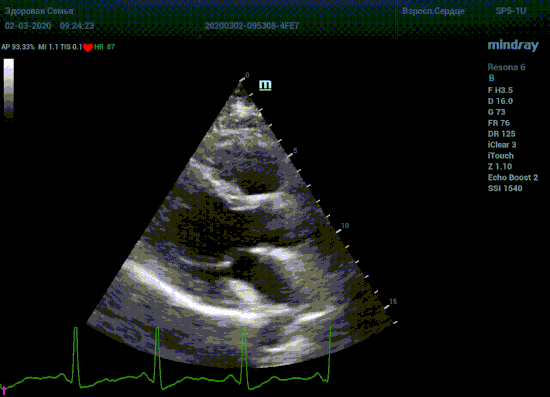

Подбор подобающей терапии и оценка её динамики на базе расчета массы миокарды рутинная задача эхокардиографии. Для измерения массы нужен кадр конца диастолы. На глазок или точно, по ЭКГ каналу, выбрать диастолу? Гипертрофия миокарда или его ремоделирование? Ремоделирование или норма? Решает каждый измеренный миллиметр, даже каждая его десятая. Лишние доли секунды приведут к началу сокращения миокарда и его утолщению, в результате -гипердиагностика.

Терапия наиболее широкая область применения, однако взрослая кардиохирургия так же важное направление современной медицины. Оперировать аортальный стеноз, или же площадь клапана достаточная? Необходимо рассчитать площадь аортального клапана по уравнению непрерывности потока. Для этого нужно измерить на зуме выносящий тракт левого желудочка (LVOT) в середине систолы. Будем угадывать момент или возьмем середину Т зубца по ЭКГ? Доверимся интуиции при определении показаний к оперативному лечению или науке?